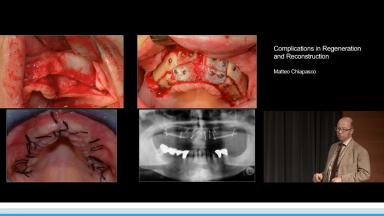

- describe prosthetic complications and their solution